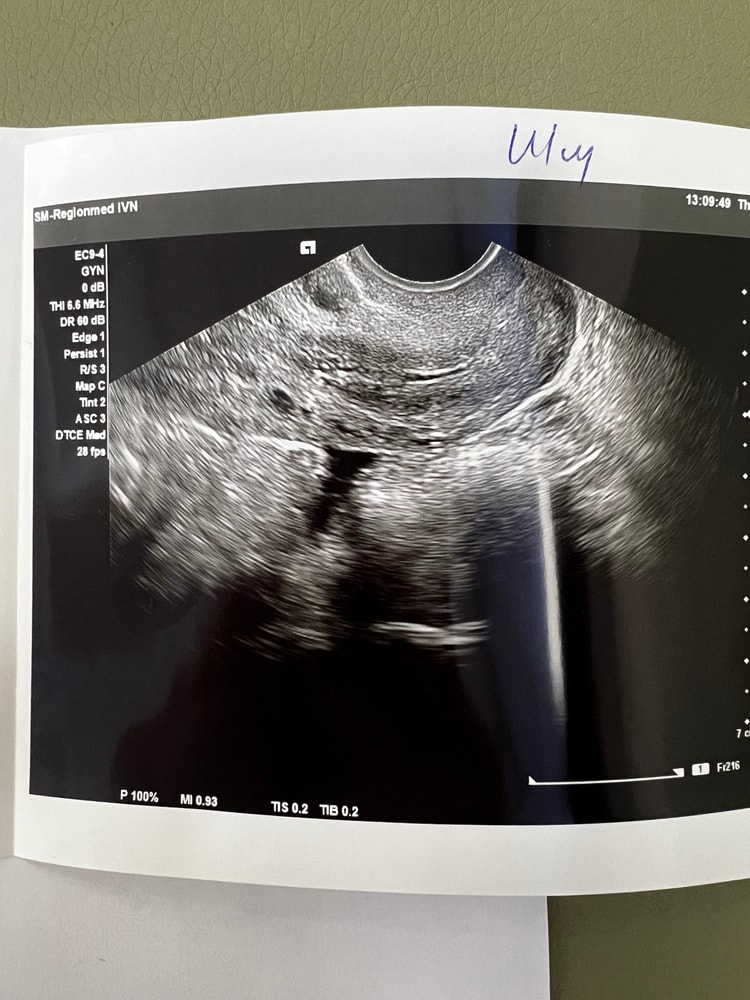

Могу сказать по своему опыту - после ЗБ была гематометра, у меня ее было видно сразу, и она не проходит безболезненно. Могла бы предположить, что у вас могут быть остатки плода, но опять же по своему опыту - остатки видно на любой день цикла. Судя по фото ниже, у меня через несколько месяцев после ЗБ на узи нашли что-то похожее - под вопросом ставили эндометриодную гетеротопию. Большего предположить не могу, к сожалению, лучше сходить к врачу, гематометра и остатки плода - это довольно опасно.

случится чудо, нашла бумажки по УЗИ - делала его через 3 месяца после вакуума и через 2 месяца после гистероскопии (удаляли остатки плода) - на 6 день цикла этого не было, а вот на 24 дц как раз под вопросом поставили вот эту эндометриоидную гетеротопию миометрия. Больше я на УЗИ не ходила. Сходила к врачу, она сказала, что это не страшно, это лечится установкой спирали вроде как, но я на тот момент уже была близка к повторному планированию Б, поэтому она сказала, что ничего делать не нужно. Собственно, потом я уже забеременела. единственное, добавлю - еще это может быть полип (после вакуума их развитие очень распространено), но вроде как полипы врачи на УЗИ видят сразу, если бы это был он , то вам бы сказали. Но лучше наверное еще раз сделать УЗИ в динамике и сходить к врачу.

Изображение Изображение